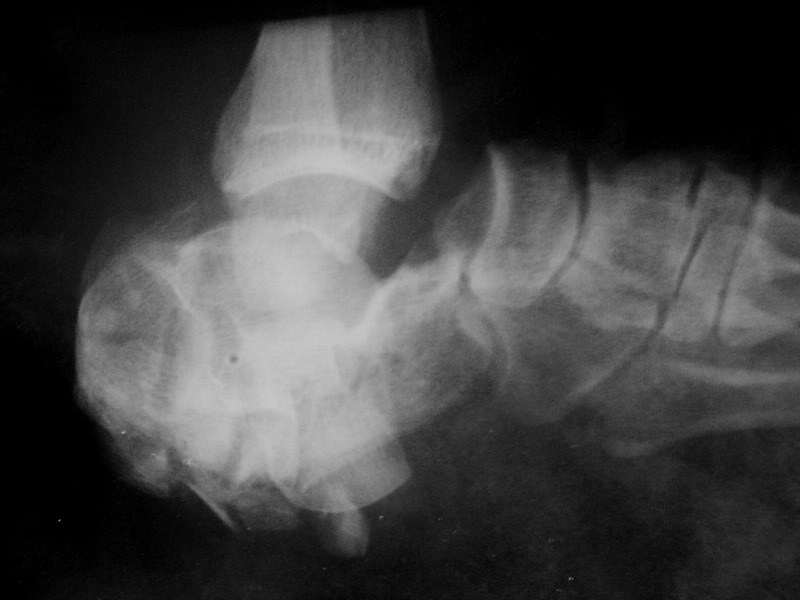

Мужчина, 57 лет. В сентябре 2008 в результате ДТП (находился за рулем автомобиля, лобовое столкновение),

получил травму левой стопы: Закрытый многооскольчатый перелом пяточной кости, вывих стопы в суставе Шопара.

Лечился в районе скелетным вытяжением за пяточную кость. Процесс осложнился околоспицевой инфекцией. Сейчас в области

пяточного бугра свищ со скудным гнойным отделяемым. В течение двух дней получает линкомицин. Планируется аппаратный артродез.